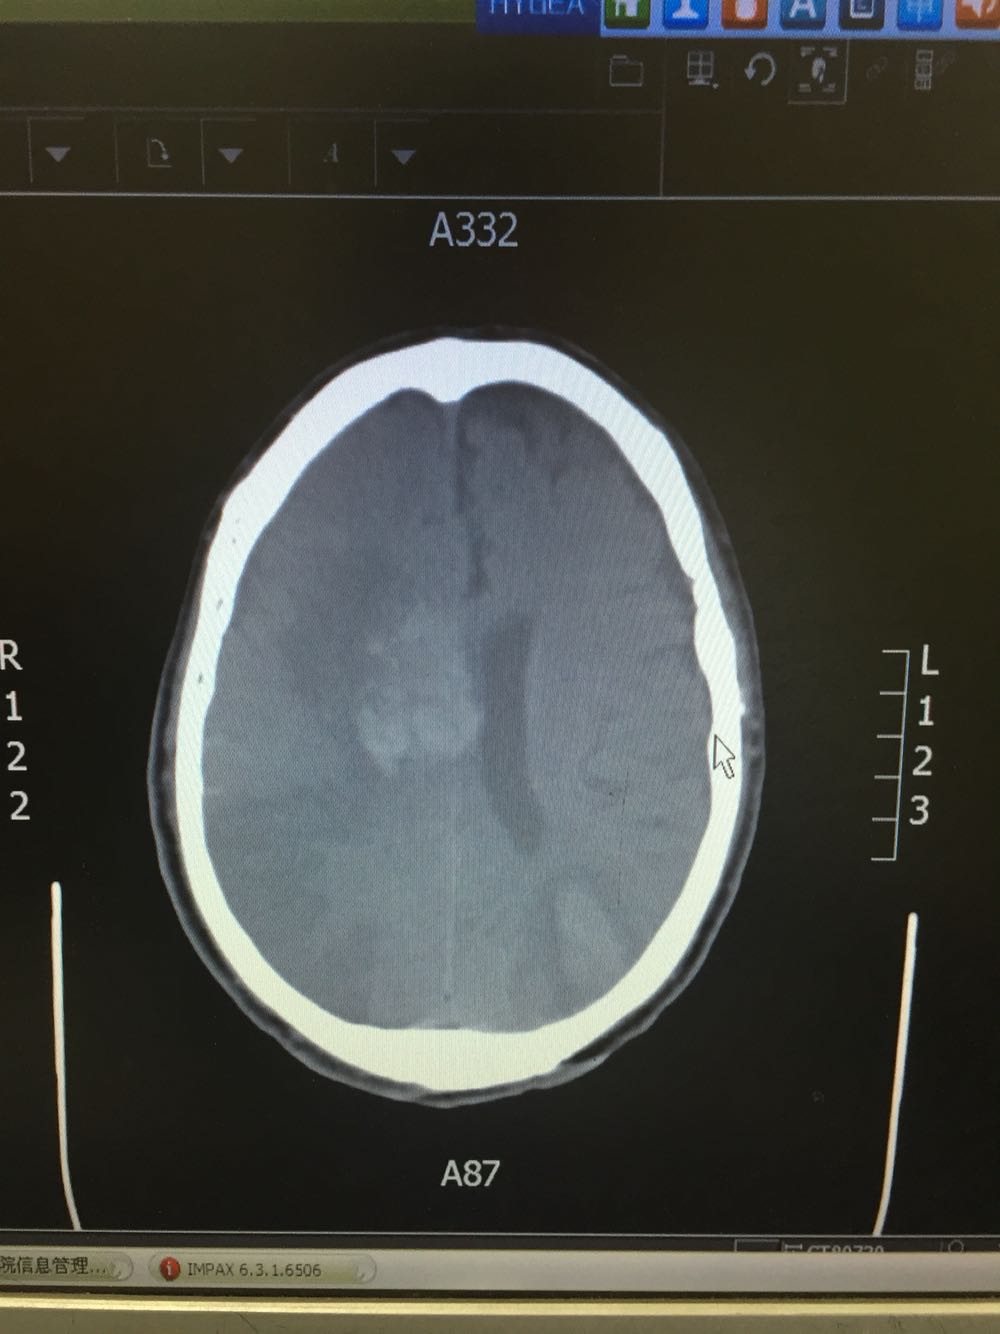

查体:血压161/106mmHg,神志清楚,言语欠流利,查体合作,双瞳孔等大同圆,对光反射存在,双眼向右侧凝视,鼻唇沟对称,伸舌居中,左侧肢体肌力0级,肌张力正常,腱反射对称,双侧痛觉对称,双下肢Babinski(+)Chaddock(+),颈强(-)克氏征(-) 头CT示:脑梗死

患者入院治疗后症状一度好转,左侧肢体肌力3级+,于入院后第二日病情突然加重,伴意识障碍,头DWI示:脑梗死伴脑出血 右侧大脑中动脉闭塞。停止当前治疗方案,脱水脑保护,营养神经对症治疗。入院后第5日复查头CT示:右侧大面积脑梗死,脑出血吸收期,伴左侧枕叶脑出血。患者左侧枕叶脑出血不好解释,能否是搬运及护理时外伤所致?